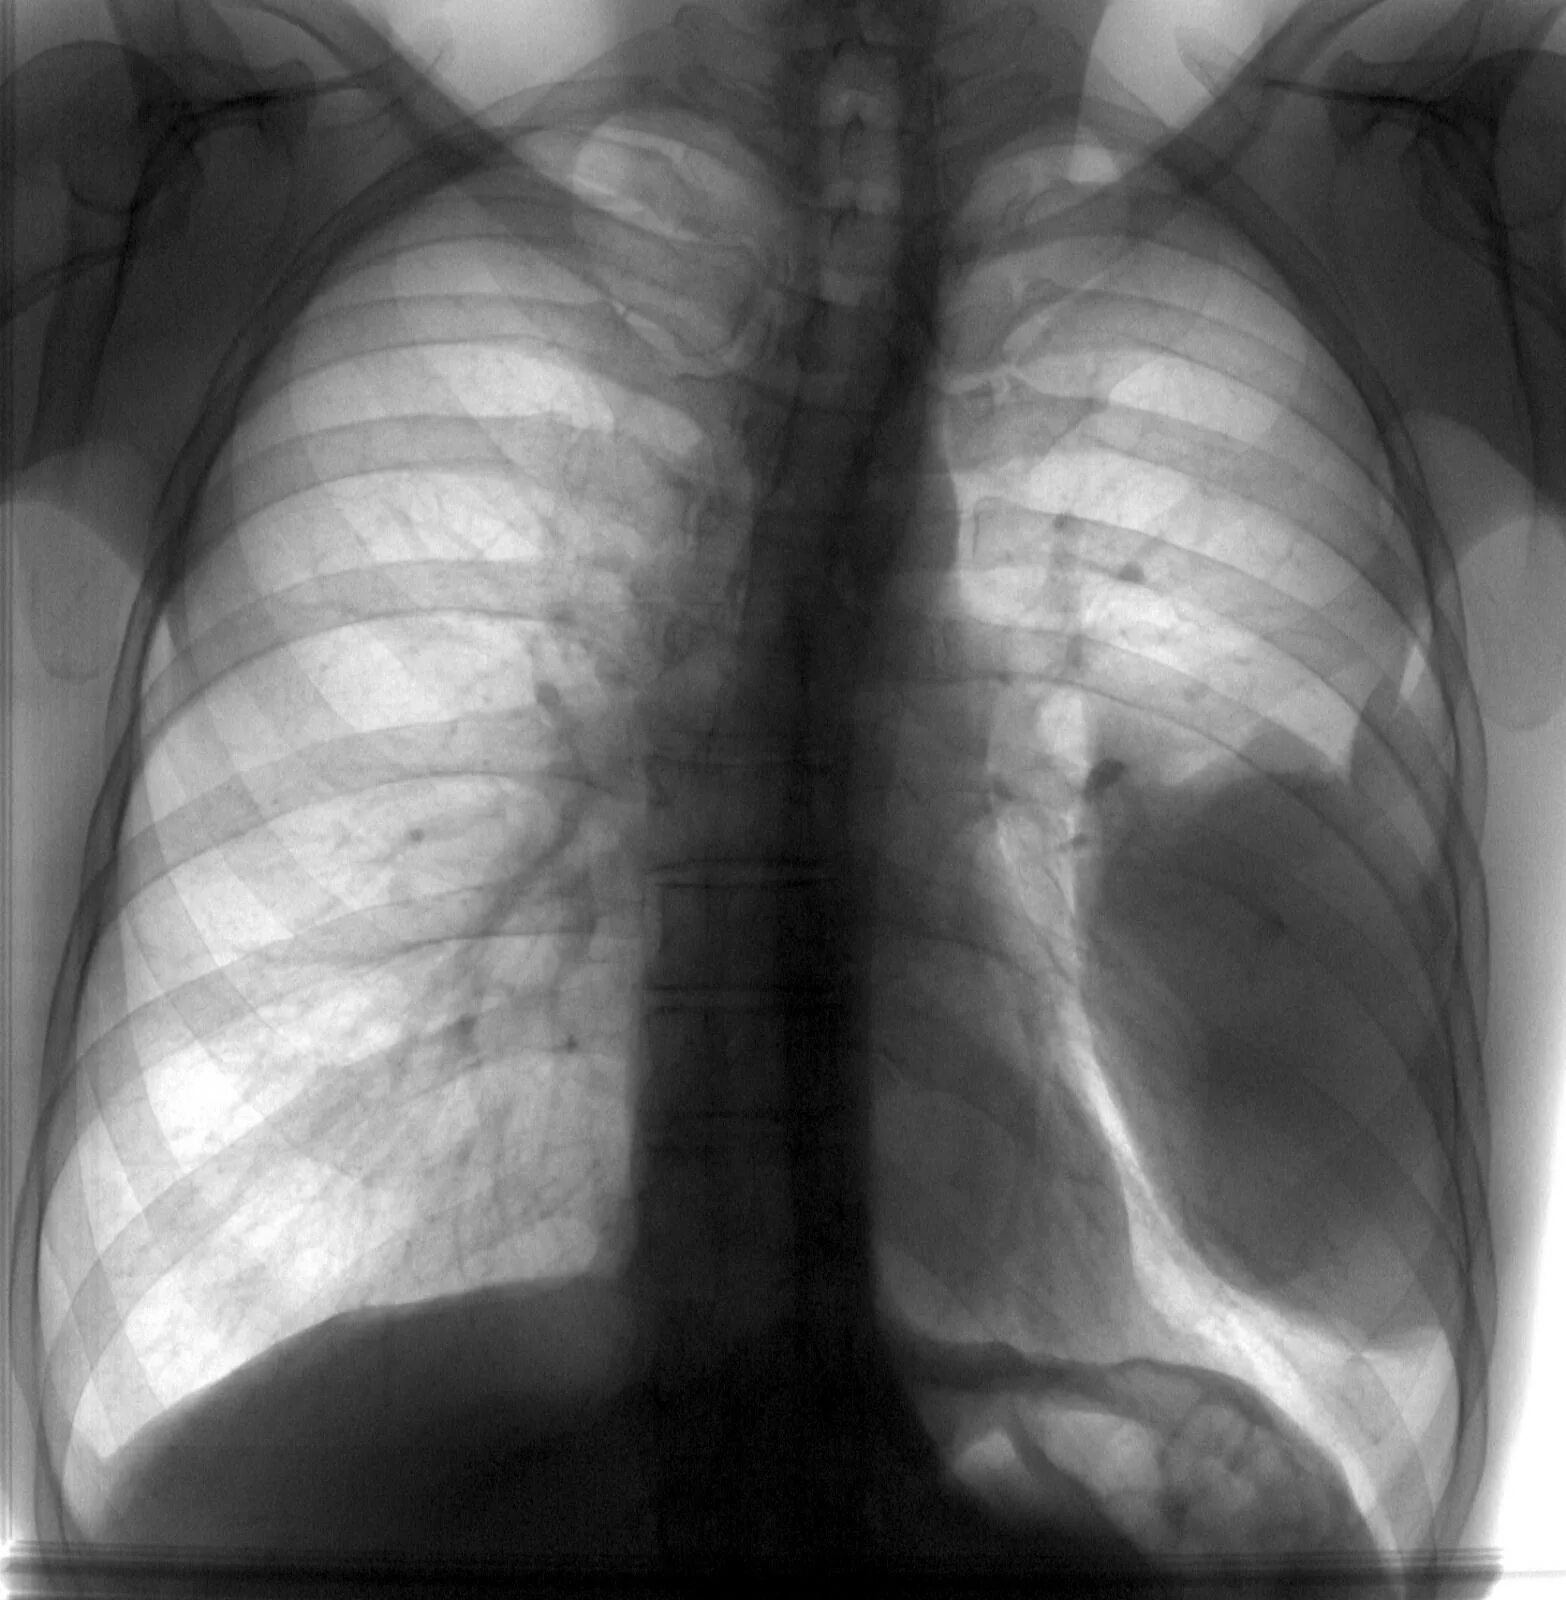

Рентгеносемиотика заболеваний плевры. рентгеносемиотика заболеваний легких. образование плевры рентген. лучевая диагностика.

Признаки сухого плеврита. лучевая диагностика заболеваний плевры. презентация. плеврит лучевая диагностика. лучевые признаки плеврита.

Выпотной плеврит симптомы. синдром поражения плевры симптомы. заболевание плевры легких.